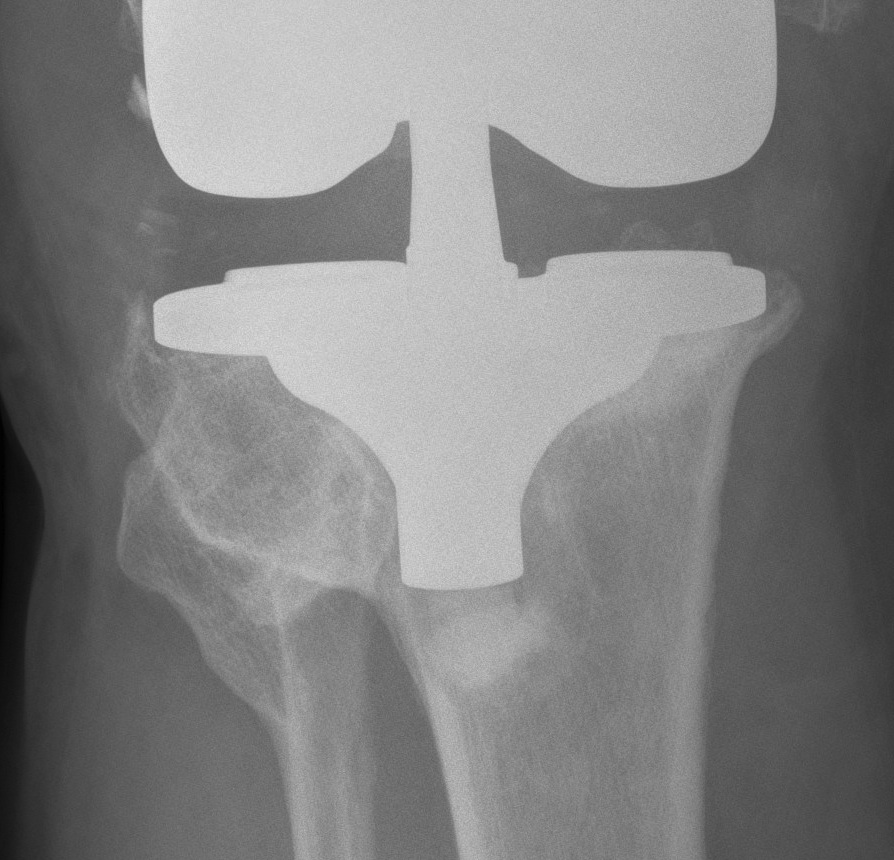

AORI / Andersen Orthopedic Research Institute

T Tibial F Femoral

1. Contained Metaphyseal Defect

Management

A. Bone graft defects

B. Standard +/- Revision TKR